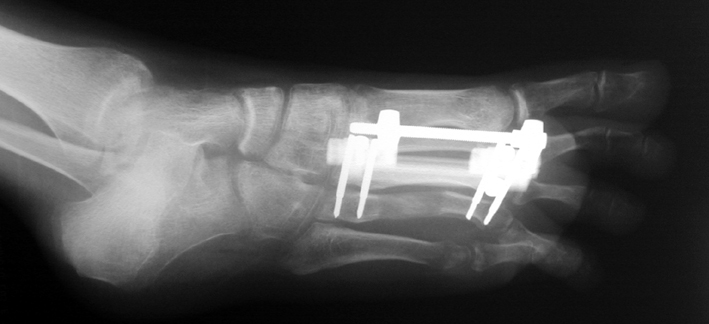

Doğuştan metakarp ve metatars kısalıklarının redavisi için pek çok teknik tanımlanmakla birlikte en çok akut uzatma sonrası kemik uçlarına greft konması ve distraksiyon osteogenezi (kallotasis) kullanılmaktadır. 1 cm.den daha fazla uzatma gereken olgularda kallotasis yöntemi önerilmektedir. Kliniğimizde de metatars ve metakarp uzatma için unilateral eksternal fiksatör ve sirküler eksternal fiksatör yardımıyla distraksiyon osteogenezi yöntemi tercih edilmektedir.